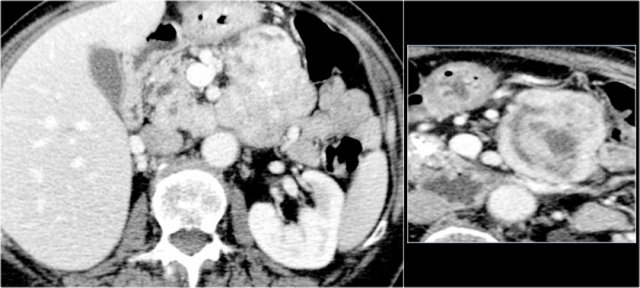

CT images of a 30 year old female with a history of a biliary pancreatitis and cholecystectomy.

She had sudden increased left abdominal pain.

US showed increased size of a cystic lesion, which was diagnosed as a pseudocyst.

The CT however showed a non-lobulated cystic lesion in the pancreatic tail with internal enhancing septation without connection to the pancreatic duct (fig).

Continue with the MRI...

The T1W-image post gadolinium better depicts the internal septations.

Pancreatic tail resection revealed a 14 cm mucinous cystadenoma including ovarian stroma.